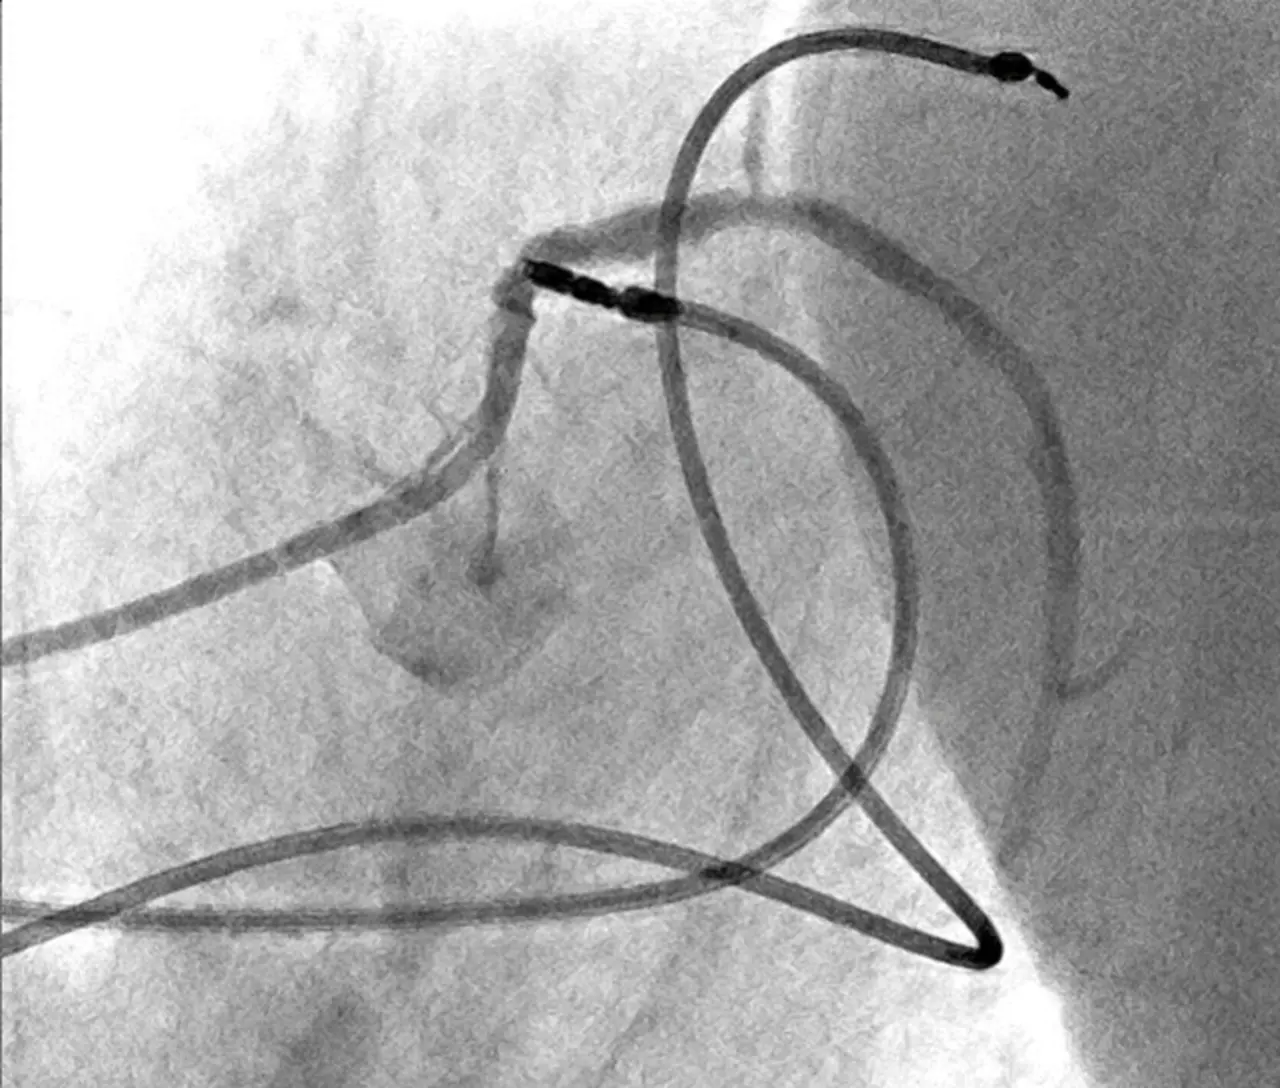

Das Angiografie-System ermöglicht eine gute Darstellung der verwendeten Instrumente wie beispielsweise diagnostischem Katheter oder Ablationskatheter.

Für gewöhnlich kommunizieren Angiographie- und Mapping-System über ein elektromagnetisches Feld miteinander, was mit einer Bildstörung einhergeht – statt einer klaren Landkarte des Herzens sieht man dann ein von Streifen überlagertes Bild. Artis icono biplane kann diese Bildartifakte reduzieren und ermöglicht eine gute Darstellung der verwendeten Instrumente wie beispielsweise diagnostischem Katheter oder Ablationskatheter.